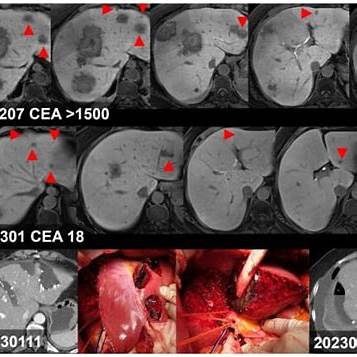

알프스 수술(ALPPS, Associating Liver Partition and Portal vein Ligation for Staged hepatectomy)은 대장암이 간으로 전이된 환자에서 간 절제술을 통해 생존율을 높이기 위한 2단계 수술법입니다. coloproctol.org+5KMA 저널+5KMA 저널+5

- 1차 수술: 간의 일부를 절제하고, 남은 간을 분리한 후 **간문맥(portal vein)**을 결찰하여 **미래 간 잔여량(FLR)**의 성장을 촉진합니다.경향신문

- 2차 수술: 약 2주 후, FLR이 충분히 성장하면 나머지 간 전이 병변을 제거하여 모든 암 병소를 절제합니다.coloproctol.org+6경북뉴스+6경향신문+6

- 부산 온종합병원, 간암환자 ‘알프스 수술’ 성공: 이 기사에서는 부산 온종합병원이 간암 환자에게 알프스 수술을 성공적으로 시행한 사례를 다루고 있습니다. 디뉴스+1경북뉴스+1

- [의료기획] 다발성 대장암 간 전이 ‘알프스 수술’: 이 기사에서는 다발성 대장암의 간 전이 환자에게 알프스 수술을 적용한 사례와 그 결과를 상세히 설명하고 있습니다. 경북뉴스